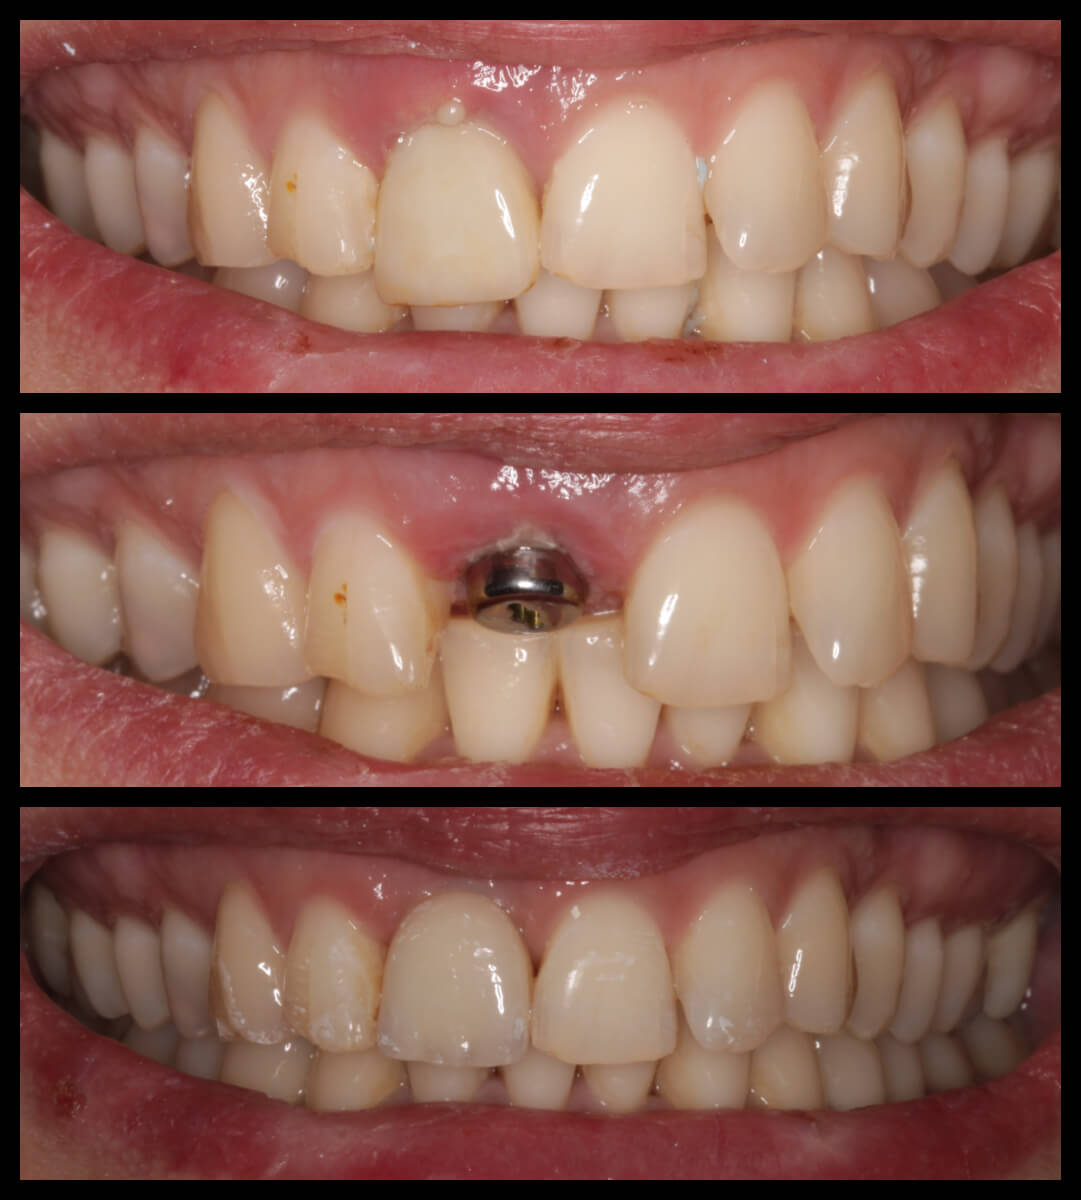

ΠΕΡΙΣΤΑΤΙΚΑ ΜΕ ΤΟΠΟΘΕΤΗΣΗ ΕΝΔΟΟΣΤΙΚΩΝ ΕΜΦΥΤΕΥΜΑΤΩΝ. ΌΠΟΥ ΧΡΕΙΑΣΤΗΚΕ ΠΡΑΓΜΑΤΟΠΟΙΗΘΗΚΕ ΑΝΑΠΛΑΣΗ ΟΣΤΟΥ ΚΑΙ ΟΥΛΙΚΩΝ ΕΛΕΙΜΜΑΤΩΝ ΜΕ ΧΡΗΣΗ ΜΟΣΧΕΥΜΑΤΩΝ ΚΑΙ PRF